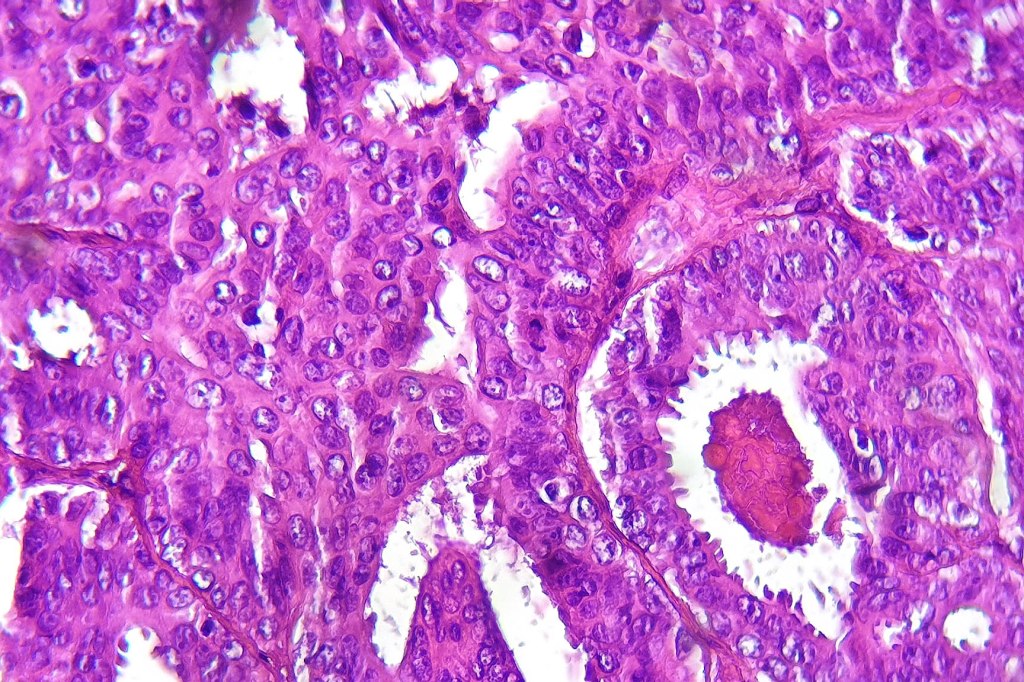

•Papillae lined by myoepithelial cells with overlying epithelial cells with eosinophilic cytoplasm showing decapitation secretion

•Solid pattern

•Mitoses can be absent or even brisk